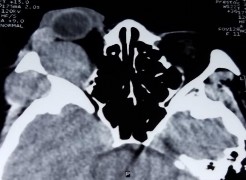

Bệnh nhân nữ, 32 tuổi, 2M: sưng nề mi góc ngoài Chẩn đoán: 2M: Quá sản lympho lành tính

Bệnh nhân sưng nề mi cách vào viện 1 tháng (A). Bệnh nhân đã điều trị nhiều đợt bằng kháng sinh, chống viêm đỡ nhưng tái phát. Hình ảnh cắt lớp vi tính có khối u góc trên ngoài ở cả hai mắt (C, D). Kết quả giải phẫu bệnh là quá sản lympho lành tính (E: HE x 100, F: HE x 200). Bệnh nhân đỡ sưng nề mi mắt rõ sau khi điều trị corticoid uống giảm liều (B).